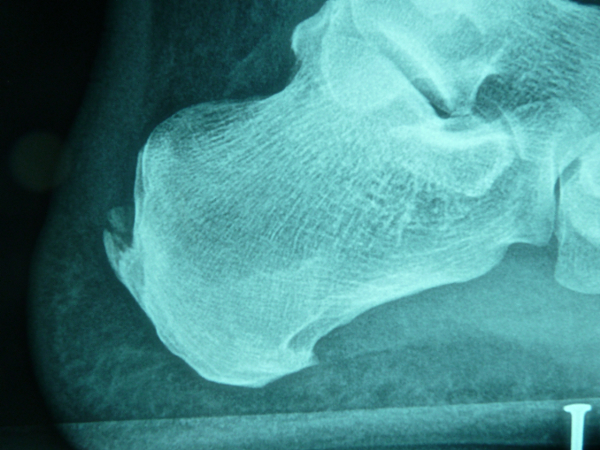

Exemple d'excision d'ossification et réinsertion d'Achille gauche:

Le tendon est incisé verticalement en son milieu et les ossifications sont dégagées et enlevées.

Elles siègent le plus souvent sur le bord latéral.

L'angle postérieur de la tubérosité est réséqué obliquement.

Quand l'ablation de l'ossification intra-tendineuse a entraîné une désinsertion large du tendon, la réinsertion tendineuse est effectuée par une suture sur une ancre intra-osseuse (si possible résorbable).